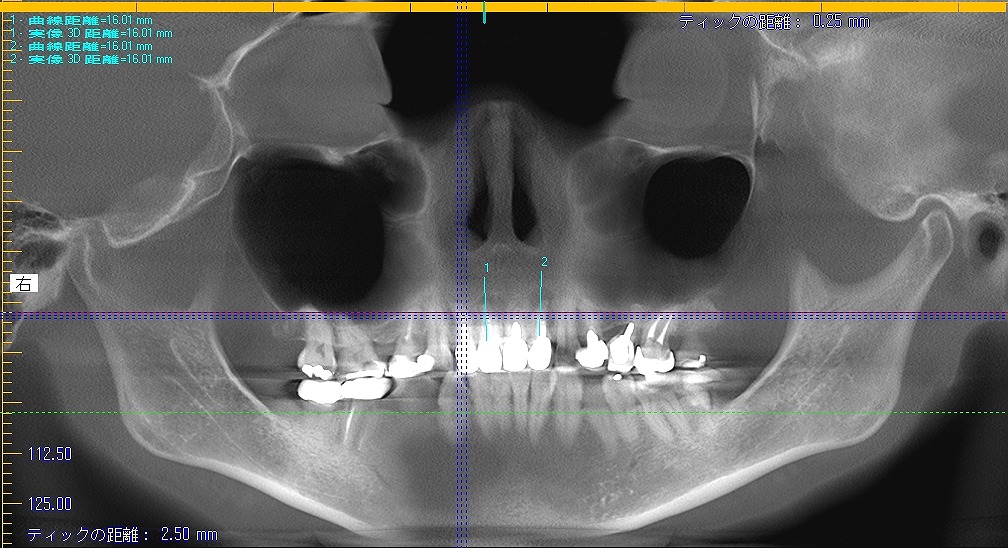

術前のパノラマになります